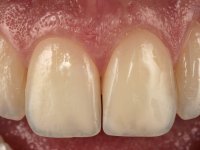

Paciente do sexo feminino, com 27 anos, não fumadora, apresentava uma restauração com resina composta tipo “Classe IV”, no angulo mesial do dente 2.1. A restauração não satisfazia esteticamente e fraturava com frequência. O bordo incisal do incisivo central direito e o remanescente natural do incisivo central esquerdo apresentava uma caracterização bastante marcada. Várias áreas de translucidez que tornariam a reabilitação bastante exigente sobre o ponto de vista técnico e estético. Na área da fratura não havia dentina exposta. A paciente gostava que a reabilitação tivesse uma abordagem o mais conservadora possível.

Realizou-se uma pré impressão em silicone para posteriormente ser feita uma restauração provisória em resina composta de polimerização “dual”. Seguidamente foi removida toda a restauração e realizado o preparo dentário. Este preparo consistiu na planificação do angulo dentário e na preparação ligeira da superfície palatina. A superfície palatina foi preparada para um assentamento sem interferências. Foi realizada uma impressão com dupla mistura e dupla viscosidade e de seguida foi feita uma restauração provisória em resina de polimerização “dual” sem qualquer tipo de adesão. Em laboratório, realizado o modelo de trabalho foi confecionada uma micro restauração de cerâmica feldespática. Essa peça de cerâmica utilizou essencialmente a superfície palatina mesial e o angulo incisal para se estabilizar. Na superfície vestibular a peça de cerâmica sobrepunha-se á superfície vestibular dentária em cerca de 2mm. Na clínica, a restauração provisória foi removida. A superfície dentária foi devidamente preparada e a micro restauração cerâmica depois de devidamente acondicionada foi colada no dente somente com adesivo. A superfície de cerâmica que sobrepunha a superfície dentária vestibular foi cuidadosamente eliminada. Para isso foi sendo feito o seu polimento de forma progressiva com discos e pontas de borracha.